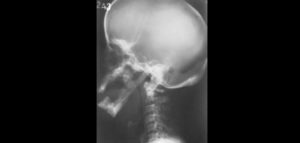

La picnodisostosis es una enfermedad rara, recesiva, autosómica perteneciente al grupo de las displasias óseas. Siendo la principal etiología la consanguinidad de los padres. Esta